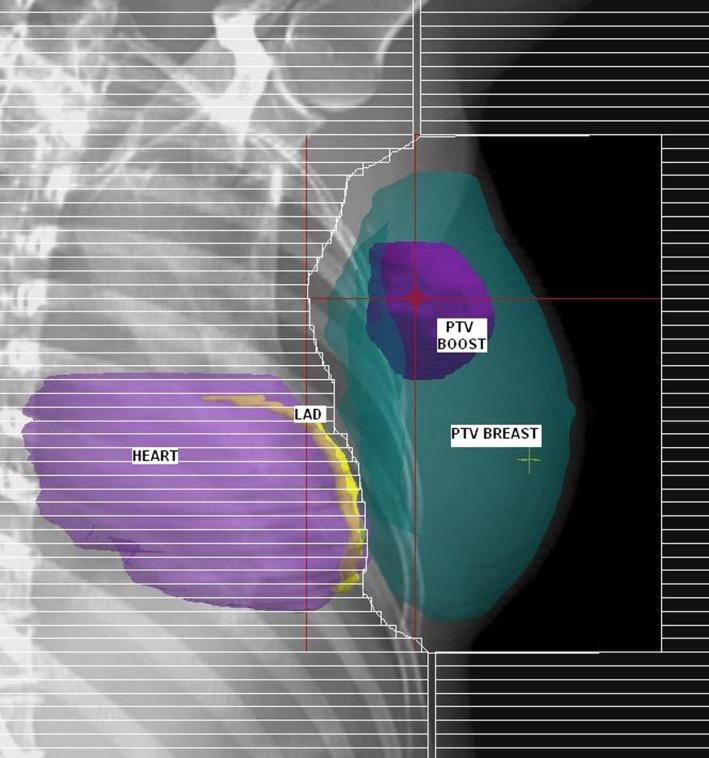

When irradiating the left breast, a small portion of the heart and left anterior descending coronary artery (LAD) are often included in the treatment field. Deep inspiration breath-hold (DIBH) techniques reduce dose to coronary structures, but are resource intensive and may not be tolerated by all patients. The aim of this study was to evaluate a simple multi-leaf collimator (MLC) modification technique with respect to target coverage and organ-at-risk sparing.

Forty nine patients with left-sided breast cancer, planned with a simultaneous integrated boost technique were retrospectively replanned with additional shielding of the LAD. Dose to the target volumes (whole breast and boost) and organs at risk (heart, ipsilateral lung and LAD) were assessed on both plans.

Significant dose reductions were observed for all organs at risk when LAD shielding was introduced, with a reduction in mean LAD dose of 7.0 Gy, mean LAD planning risk volume (PRV) dose of 5.9 Gy, maximum LAD dose of 12 Gy and mean heart dose of 0.73 Gy. Target volume coverage was clinically acceptable for 96% of patients, using the left anterior descending coronary artery shielded plan (LADSP). No difference was observed between the standard plan (SP) and LADSP in nine patients (18%).